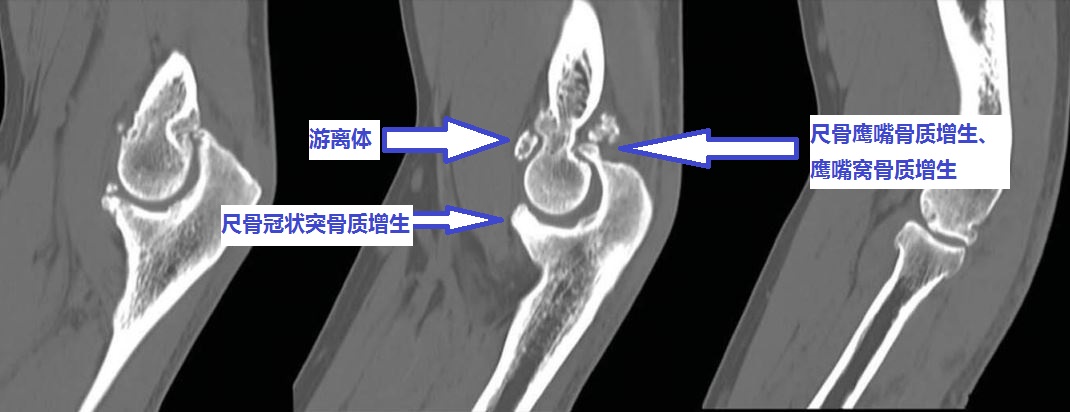

伸不直往往是因为:1、尺骨鹰嘴骨质增生;2、肱骨远端后侧的尺骨鹰嘴窝骨质增生填塞;3、肘关节前侧的关节囊挛缩;4、肘关节内的游离体卡住了;等等。

屈不下来往往是因为:1、尺骨冠状突骨质增生;3、肱骨远端前面的尺骨冠状突窝骨质增生;4、肘关节后侧的关节囊挛缩;等等。